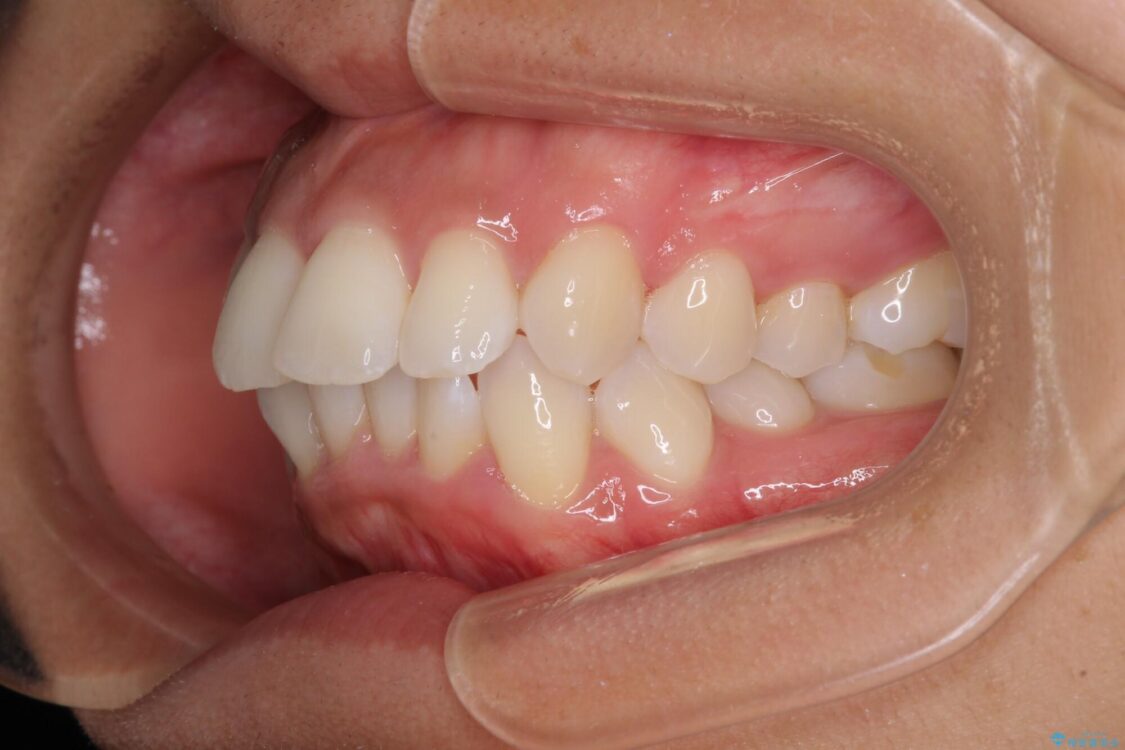

下唇が突き出るような口元の突出感が気になるとのことで来院された患者様です。

上下顎ともに前突した歯列であったので、上下ともに左右の第1小臼歯4本を抜歯し、ワイヤー装置にて矯正治療を行うこととしました。

治療前